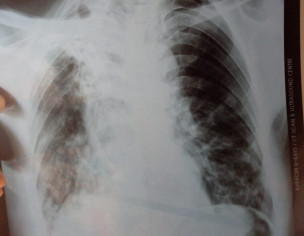

Mer3 father ko kuch din say shadid khansi xray krwaya h.. plz bata dein kya likha h isme..

is main ye hai k purani t.b ke waja sai lungs damage ho gay hain.rite wala ziada damage hai

right lung collapse hai better to consult with specialist

Right lung is collapsed

May be the patient is exposed to someone with TB without knowing or a chain smoker